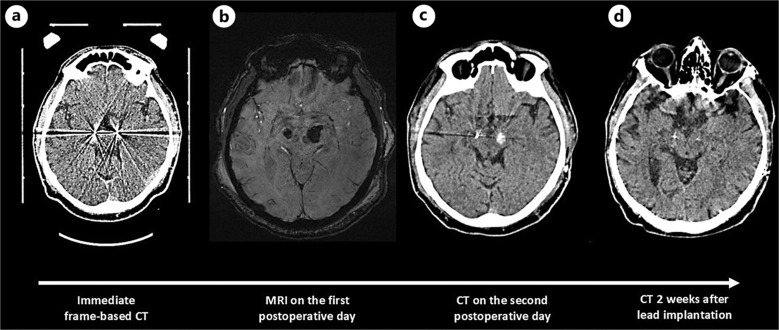

Case presentation: We present a rare case of a 67-year-old male with PD who developed delayed ICH after undergoing bilateral STN DBS. Initially, the patient showed no neurological deficits postoperatively, with imaging confirming correct lead placement and no signs of hemorrhage. However, on the second postoperative day, the patient developed sudden right-sided hemiparesis. A CT scan revealed ICH alongside the left lead. The hemorrhage was managed conservatively, and the patient underwent extensive physical therapy, leading to significant improvement. Over the next 2 weeks, the patient's condition improved, and follow-up CT scans showed complete resolution of the ICH. At this point, the left lead stimulation was initiated, further improving the patient's PD symptoms. This case illustrates the potential for delayed ICH following STN DBS, emphasizing the need for ongoing monitoring and individualized treatment strategies.